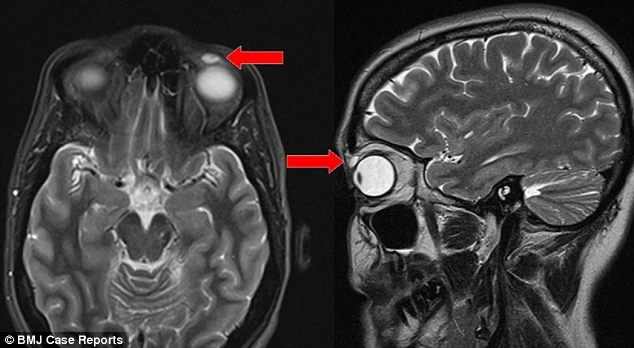

Bản chụp MRI cho thấy trên mí mắt bệnh nhân có một nốt nhỏ, kích thước 8mm x 4mm x 6mm, ban đầu bác sĩ cho rằng chỉ là mụn bọc. Tuy nhiên, khi lấy dị vật ra, các bác sĩ phẫu thuật vô cùng kinh ngạc khi phát hiện ra khối u này thực sự là một cái kính sát tròng đã rạn vỡ.